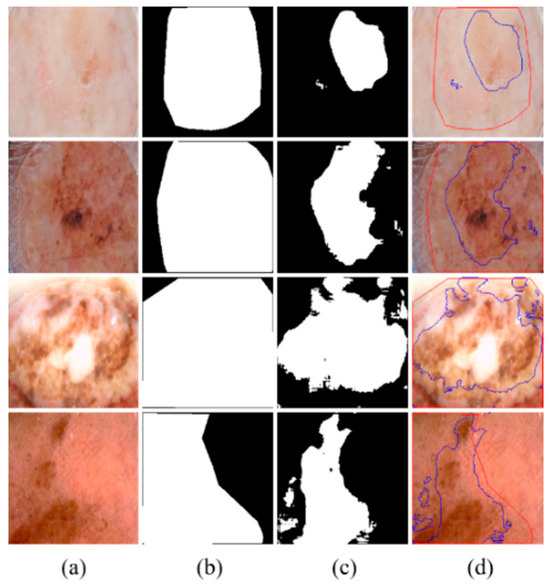

MSDTCN-Net: A Multi-Scale Dual-Encoder Network for Skin Lesion Segmentation

Background/Objectives: Accurate segmentation of skin lesions is essential for early skin cancer detection. However, traditional CNNs are limited in modeling long-range dependencies, leading to poor performance on lesions with complex shapes. Methods: We propose MSDTCN-Net, a dual-encoder network that integrates ConvNeXt and Deformable [...] Read more.

Background/Objectives: Accurate segmentation of skin lesions is essential for early skin cancer detection. However, traditional CNNs are limited in modeling long-range dependencies, leading to poor performance on lesions with complex shapes. Methods: We propose MSDTCN-Net, a dual-encoder network that integrates ConvNeXt and Deformable Transformer to extract both local details and global semantic information. A Squeeze-and-Excitation (SE) mechanism is introduced to adaptively emphasize important channels. To address scale variation in lesions, we design a Multi-Scale Receptive Field (MSRF) module combining multi-branch and dilated convolutions. Furthermore, a Hierarchical Feature Transfer (HFT) mechanism is employed to guide high-level semantics progressively to shallow layers, enhancing boundary reconstruction in the decoder. Results: Extensive experiments on the ISIC 2016, ISIC 2017, ISIC 2018, and PH2 datasets show that MSDTCN-Net achieves competitive performance across metrics including IoU, Dice, and ACC, validating its effectiveness and generalization in skin lesion segmentation. Conclusions: MSDTCN-Net effectively combines local and global feature extraction, multi-scale adaptability, and semantic guidance to achieve high-accuracy skin lesion segmentation, demonstrating its potential in clinical diagnostic applications. Full article

(This article belongs to the Section Machine Learning and Artificial Intelligence in Diagnostics)

Show Figures

Figure 1